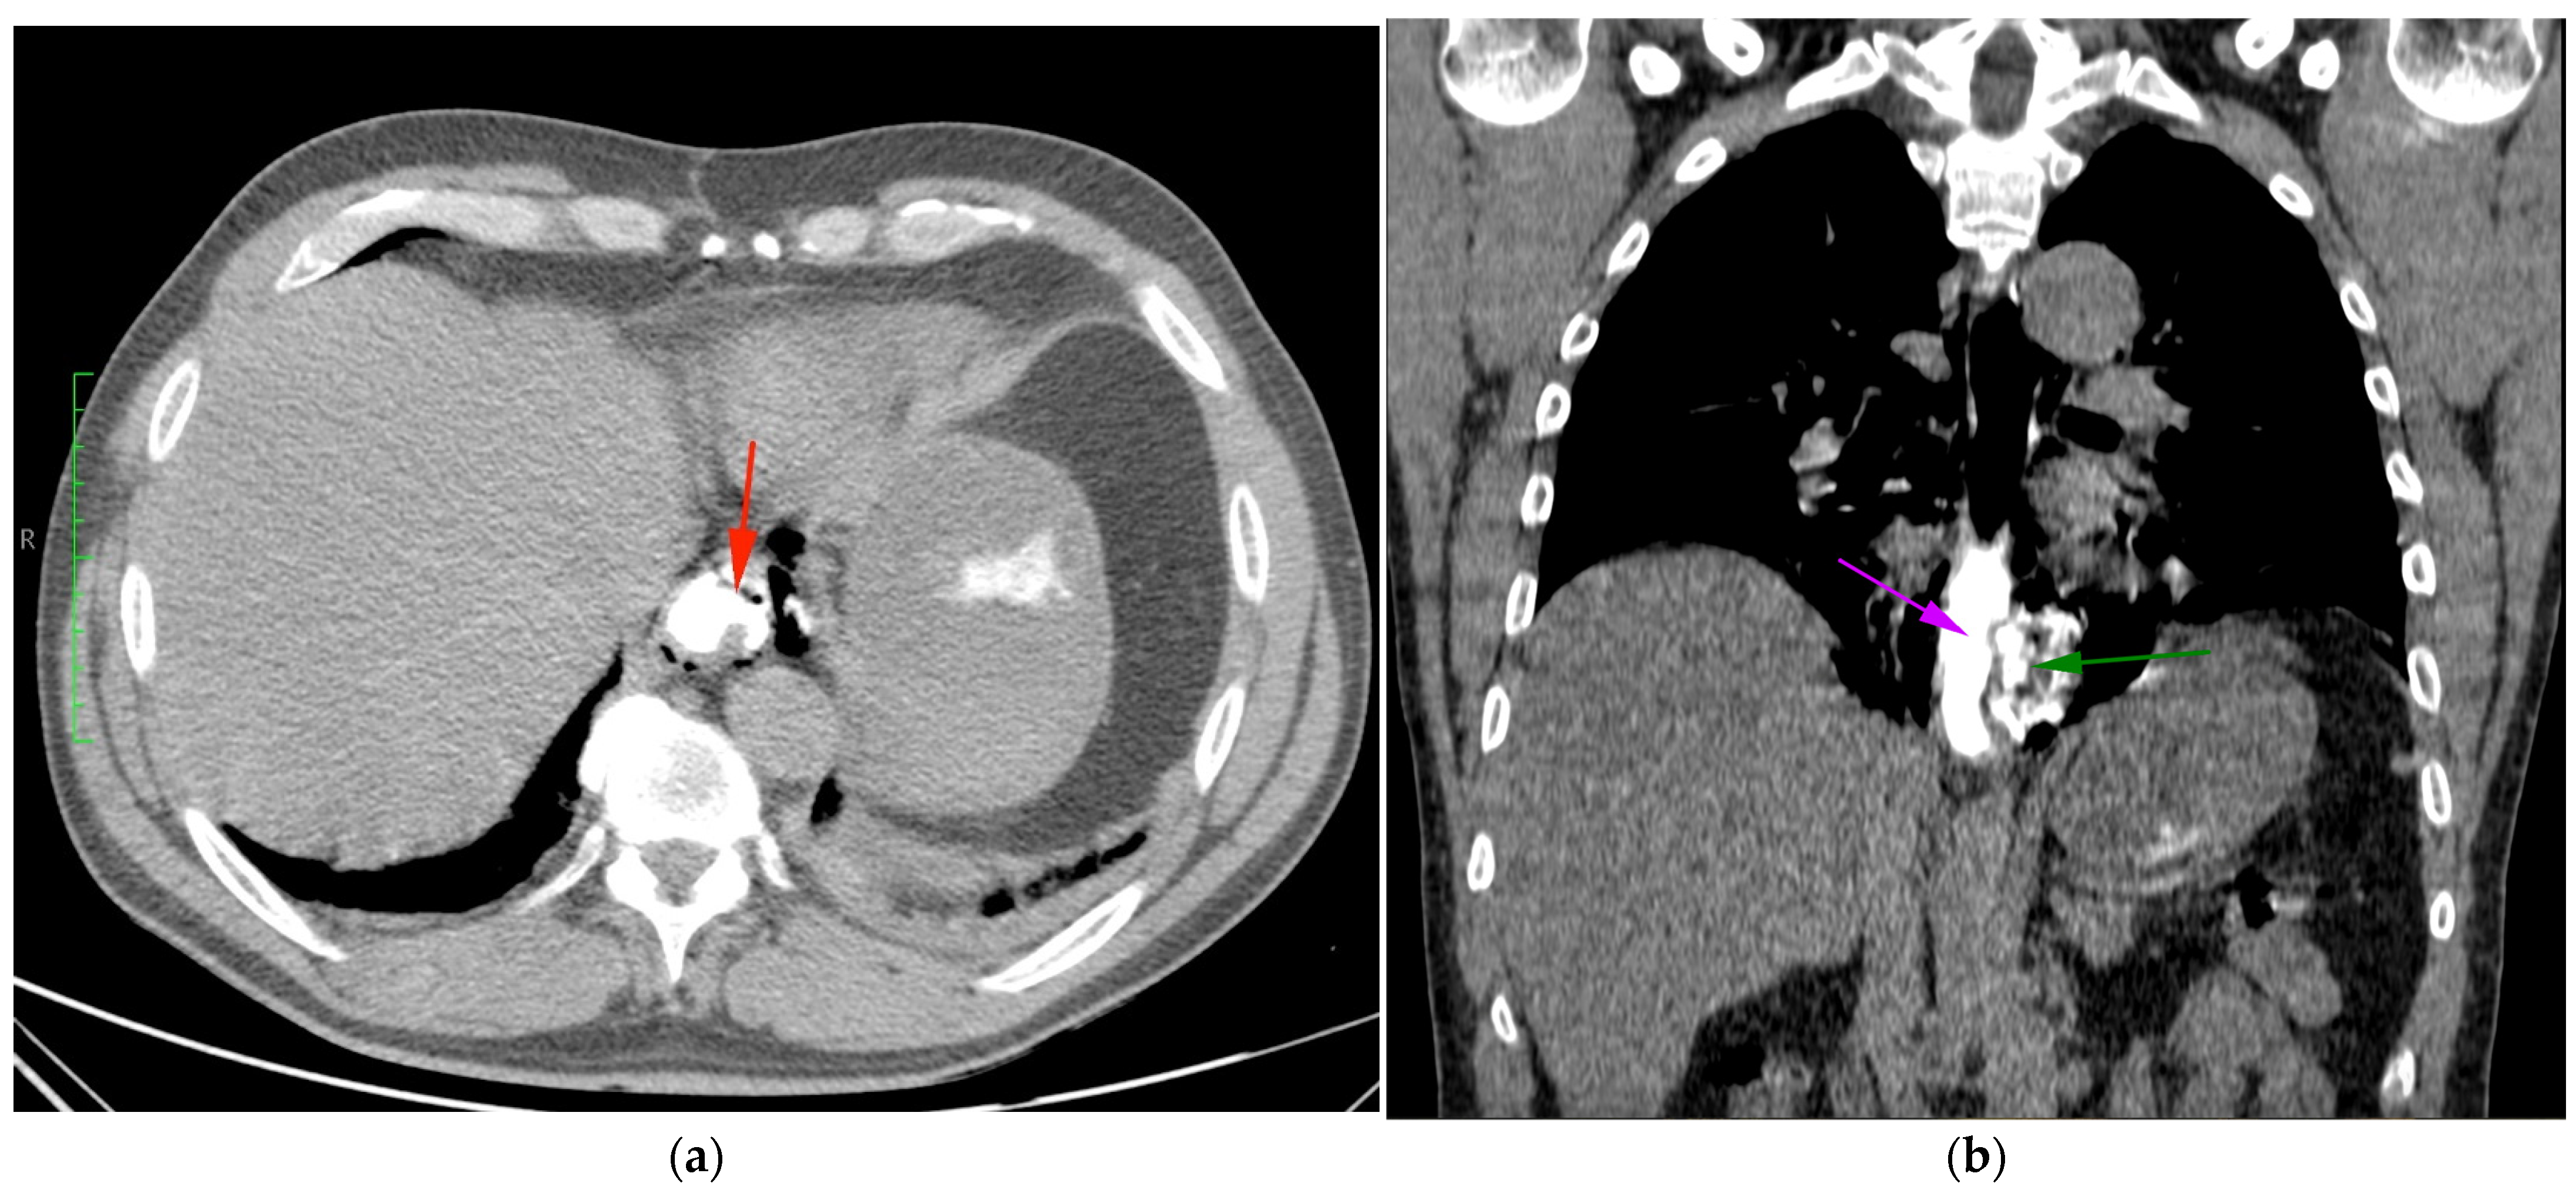

2. Case